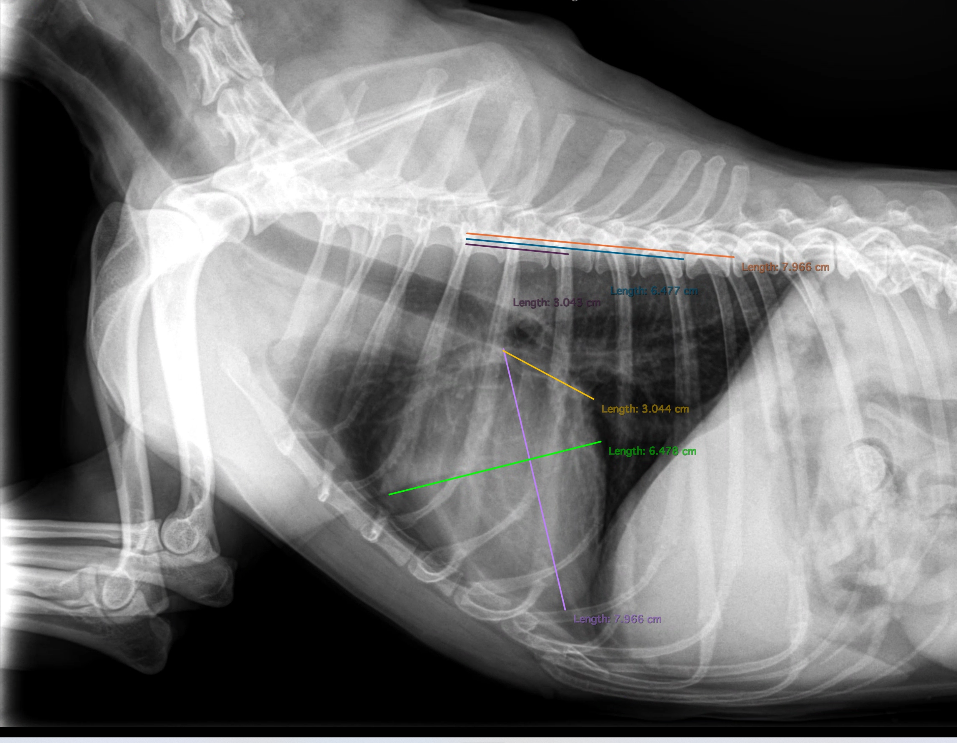

トップ写真をご覧ください。

基本的には右下ラテラル像での気管分岐部から心尖部への長軸線(紫色の線)を引き、それに直行する短軸(緑色の線)も測定します。

この長軸線と短軸線が第4胸椎から何椎体分かというのを小数点以下1桁まで測定したものがVHSです。

トップ写真の黄色線はVLASという左心房の大きさの指標を測定している線です。

トップ写真のVHSは11.1です。

10.2どころか10.5も明らかに超えていますので心拡大ですね!となるかと言えばなりません。

何故ならこの子はミニチュアシュナウザーだからです。